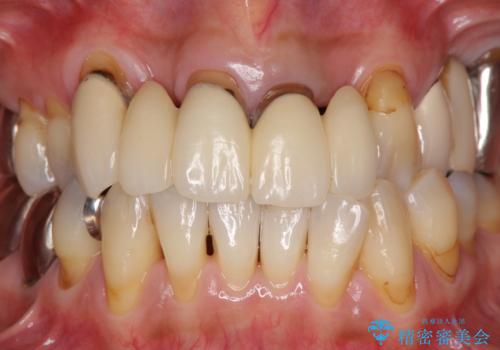

露出していた歯根や金属の縁が見えてしまい、なかなか口を開けて笑うことができなかったのですが、歯肉の位置に縁を合わせることで自然な仕上がりとなりました。

ブリッジの隙間にものが詰まったり、空気が抜けたりすることも無くなり、話しやすさも改善することができました。

露出していた歯根が覆われるため、歯冠が長く見えてしまうことが懸念されましたが特に気になることはなく、患者様には大変満足していただきました。